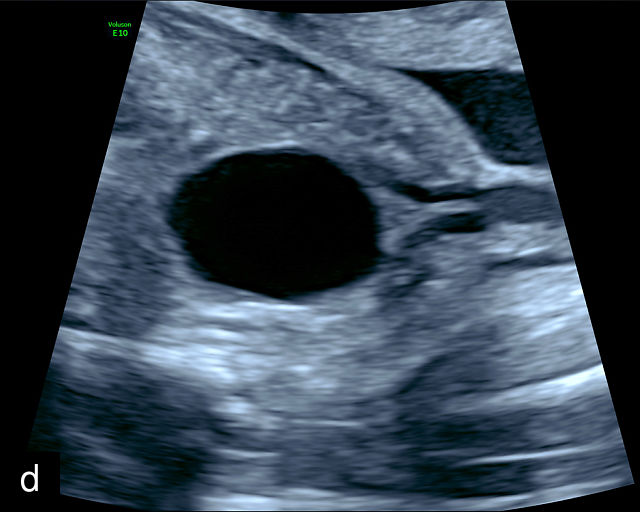

21

(a) Type-1 vasa previa. Photograph after delivery showing the umbilical cord inserting into the membranes through which unprotected fetal vessels run to insert into the placental edge. (b) Type-2 vasa previa. Photograph after delivery showing bilobed placenta with unprotected fetal vessels running though the membranes between the lobes. (c) Type-3 vasa previa in a twin pregnancy. Photograph after delivery showing unprotected vessels running through the membranes from one edge of the placenta to another (arrow). (d) Transabdominal grayscale ultrasound of the lower uterine segment showing a linear hypoechoic structure (fetal vessel) running over the cervix (c) indicating vasa previa (Type 2). b, bladder; h, fetal head. (e) Transabdominal color Doppler ultrasound of the lower uterine segment showing fetal vessels (arrow) running over the cervix (c) indicating vasa previa (Type 2). (f) Transabdominal ultrasound with color flow and pulsed-wave Doppler of the lower uterine segment showing a fetal vessel running over the cervix (c) indicating vasa previa (Type 2). Pulsed-wave Doppler demonstrates an umbilical arterial waveform. (g) Transvaginal grayscale ultrasound with showing a Type-2 vasa previa. There are two placental lobes, an anterior (a) and a posterior (p) lobe. There is a linear and circular hypoechoic structure (arrow) running over the cervix (c) between the lobes. (h) Transvaginal grayscale ultrasound image of vasa previa. A hypoechoic linear structure (arrow) is seen running through the membranes over the cervix (c). h, fetal head. (i) Transvaginal grayscale ultrasound of vasa previa. Hypoechoic circular and linear structures are seen close to the internal os. (j) Transvaginal color Doppler ultrasound image of vasa previa. A fetal vessel is seen running through the membranes over the internal os (arrow) of the cervix (c). h, fetal head. (k) Transvaginal ultrasound with color Doppler showing a Type-2 vasa previa. There are two placental lobes, an anterior and posterior lobe (pl). Fetal vessels run over the cervix between the lobes. (l) Transvaginal color flow ultrasound with pulsed-wave Doppler image of vasa previa. Color Doppler shows flow through the vessel and pulsed-wave Doppler shows a fetal umbilical venous waveform. (m) Transvaginal color ultrasound with pulsed-wave Doppler image of vasa previa. Color flow Doppler shows flow through the vessel and pulsed-wave Doppler shows a fetal umbilical arterial waveform. (n) Transvaginal three-dimensional ultrasound with color Doppler image of vasa previa. h, fetal head; c, cervix.

12